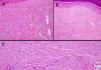

A) Múltiples luces vasculares en la dermis, rodeadas de un infiltrado inflamatorio linfocitario correspondientes a la lesión de sarcoma de Kaposi previo al inicio del tratamiento con imiquimod. B) y C) Hiperplasia endotelial y fibrosis en ausencia de signos de sarcoma de Kaposi en la lesión tratada.

Durante el tratamiento con imiquimod el paciente experimentó escasa inflamación en la zona de aplicación, y al mes del inicio del tratamiento las lesiones se resolvieron prácticamente, siendo la curación completa a las 10 semanas (figs. 1B, 2B y C).